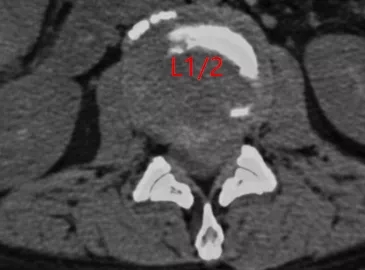

? 術(shù)前CT

入院時(shí),患者臥床不能自理,雙下肢劇烈疼痛讓患者連續(xù)幾個(gè)晚上睡覺(jué)都十分困難。查體顯示雙側(cè)髂腰肌肌力II級(jí),雙側(cè)股四頭肌力III級(jí),遠(yuǎn)端肌力輕度減低。鞍區(qū)感覺(jué)減退,肛門(mén)括約肌輕度松弛,小便費(fèi)力。綜合影像學(xué)檢查結(jié)果診斷為腰1/2椎間盤(pán)脫出,馬尾綜合癥。6月25日,在空軍軍醫(yī)大學(xué)西京醫(yī)院脊柱外科王哲主任安排下,丁坦副教授主刀實(shí)施腰1/2椎板切除減壓,髓核摘除,椎間植骨融合內(nèi)固定術(shù),手術(shù)用時(shí)2小時(shí)順利結(jié)束。